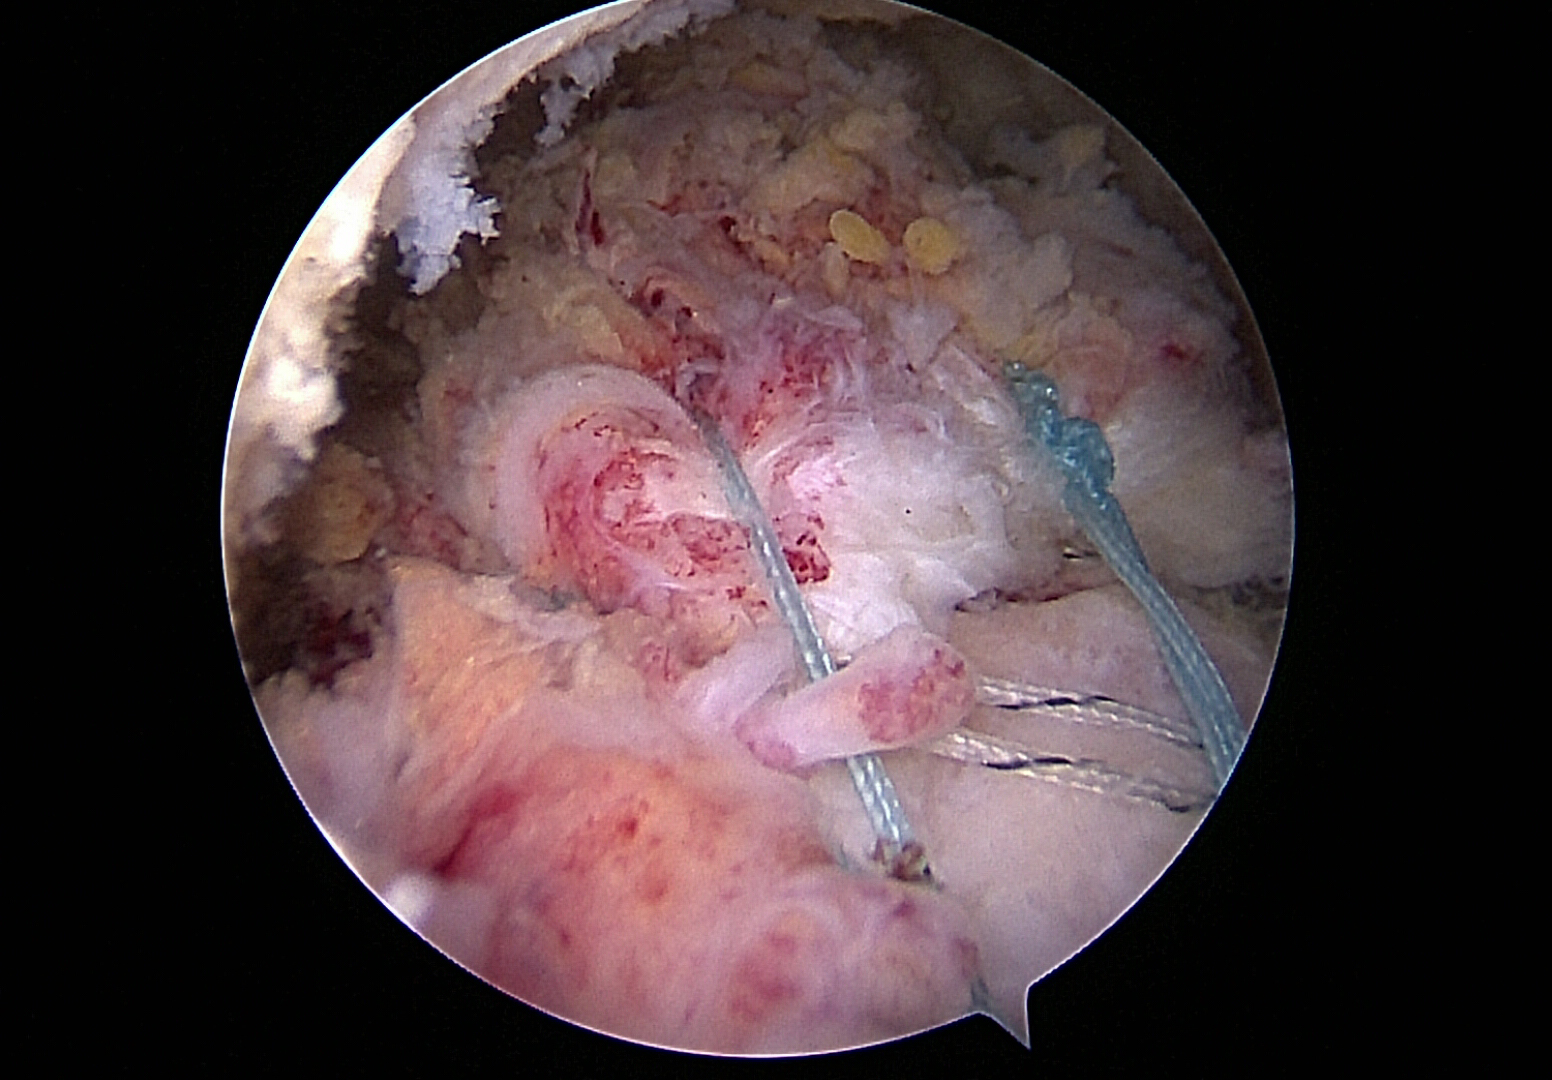

Rekonstruierte Rotatorenmanschette

Die arthroskopisch (Gelenkspiegelung) e-Rekonstruktion ist ein minimalinvasives Verfahren, bei dem die gerissenen Sehnen mit Hilfe kleiner Schnitte und einer Kamera(Arthroskopie)präzise wieder an den Knochen befestigt werden.

Diese Methode bietet zahlreiche Vorteile: geringere Gewebeverletzung, kürzere Heilungszeit, weniger Schmerzen nach der Operation und eine insgesamt schnellere Rehabilitation.